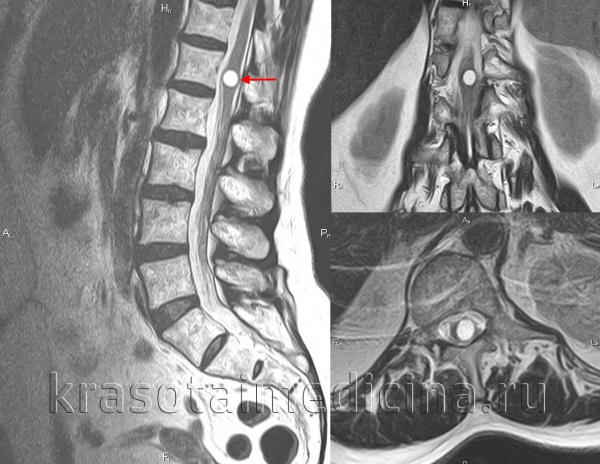

Сирингомиелия:

(слева) Массивная кавитация спинного мозга у 5,5-летней девочки, имеющей только минимальные симптомы и признаки.

(справа) Бессимптомная фистула видимая на спинном мозге, ассоциированная с мальформацией Киари I.